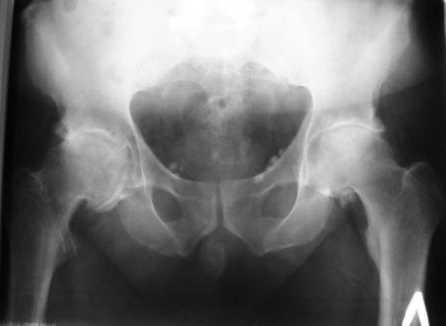

Больной Т. 56 лет, Диагноз: двухсторонний коксартроз 3-4 ст справа, 1-2 ст слева 2.10.08 выполнена операция тотальное бесцементное эндопротезирование. Использовался наружный доступ, положение на боку. Операция протекала без особенностей.

Выполнен послеоперационный ренгеноконтроль в прямой проекции. Рана зажила.